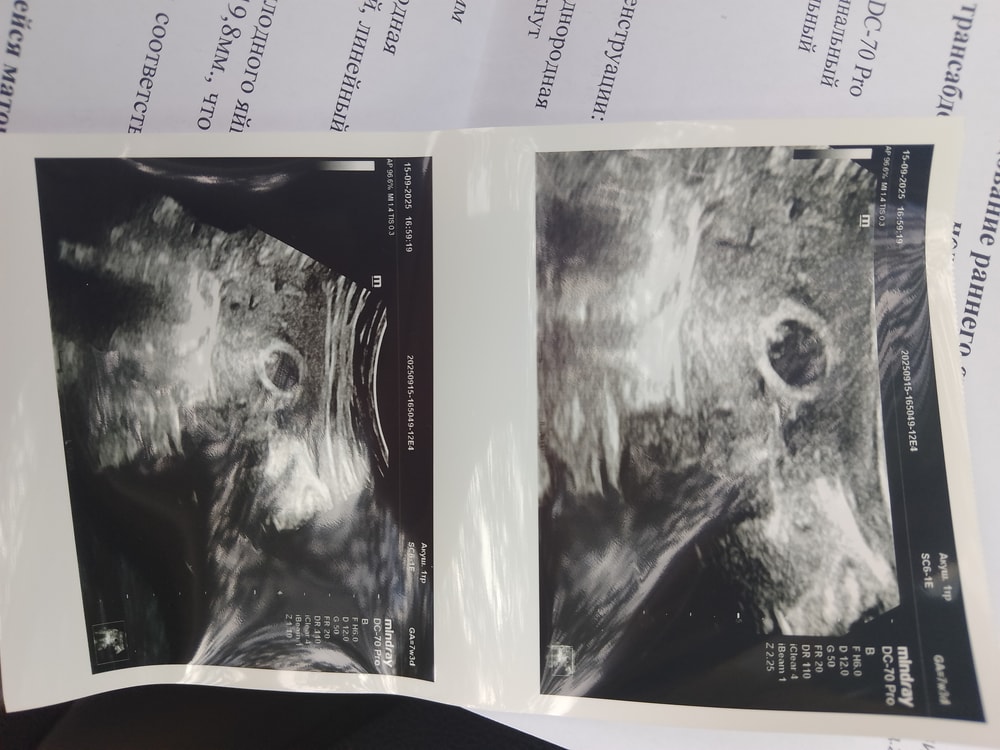

УЗИ на 34 дпп

Результаты УЗИМои приключения продолжаются. На 25 ДПП было только плодное яйцо и желточный мешочек. Вчера на 34 ДПП уже увидели эмбрион, ктр 4,1 мм и врач сказала, что в течении нескольких дней появится сердцебиение. Показывала сокращения, но зарегистрировать не удалось. Девчат, я в растерянности, чего мне ждать. Вчера отправили протокол УЗИ репродуктологу, она даже не ответила